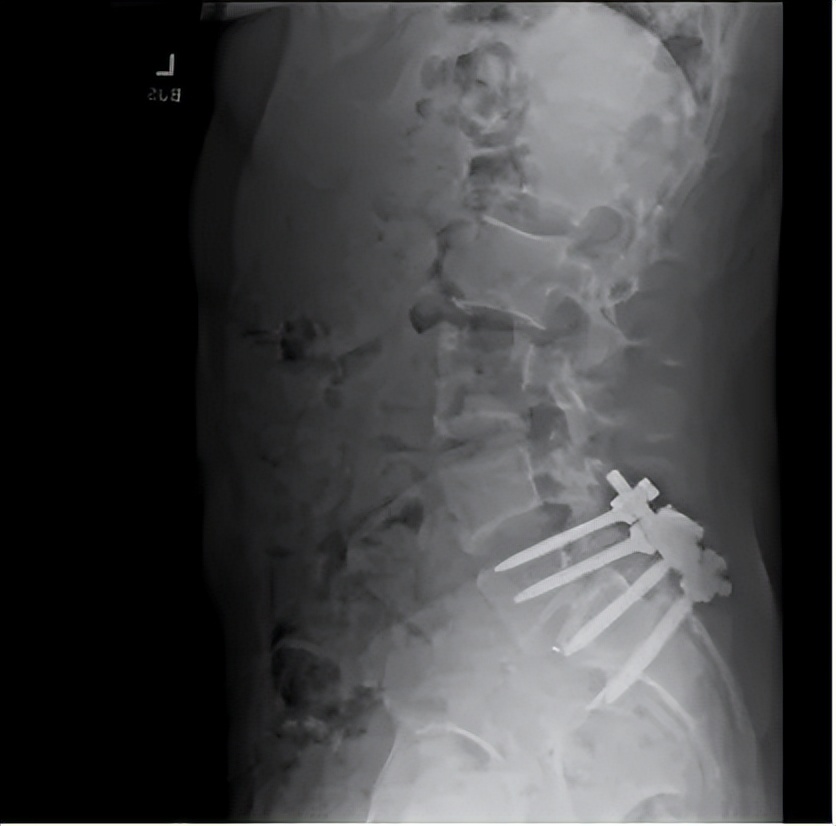

据路易吉的朋友说,路易吉患有慢性背痛,他的脊椎有点错位,并且压迫到了神经,问题“非常严重”。

据另一位知情人士说,2022年,路易吉还因在夏威夷冲浪和徒步加重了损伤。

除了造成反复的疼痛外,背痛让路易吉难以过上正常的生活,他不能和别人约会,也不能和别人发生亲密关系。

2023年,路易吉接受了手术。术后,当朋友问他手术进展时,路易吉回复“说来话长”。